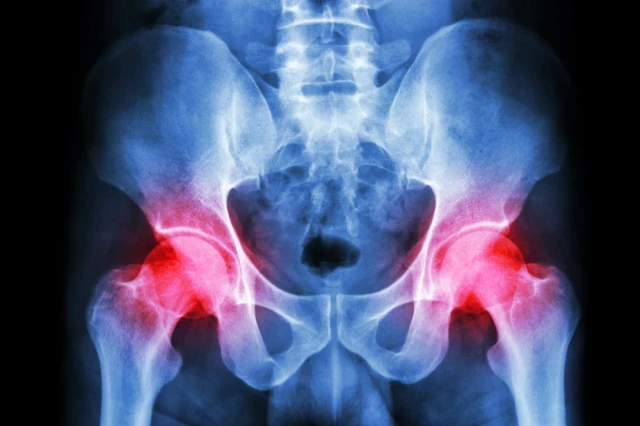

Read MoreThe Hip, Getting Older and Running

Many active Americans worry about the impact of exercise on their hips. Chris Dollar, PT, DPT, talks about the hip and how it ages with you.